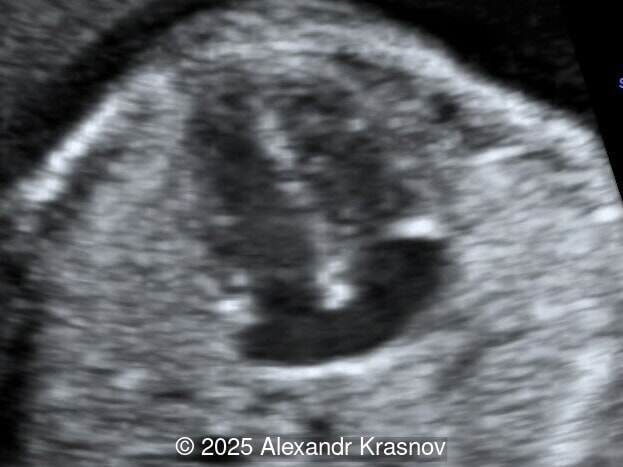

Our ultrasound showed biometry data corresponding to 21 weeks of gestation. During echocardiography, an abnormal drainage of the pulmonary veins was detected in which the pulmonary veins drain into a venous collector linked to the superior vena cava. The four-chamber view and the three-vessel view were altered and raised suspicion of a pathology. The grayscale and color Doppler images of the four-chamber view indicate a smooth posterior wall of the left atrium, increased distance between the left atrium and the descending aorta and the absence of pulmonary veins entering the left atrium (Image 1, 2; Video 1, 2). In the three-vessel view, the diameter of the superior vena cava appears larger than that of the aorta (Image 3, Video 3). In the images of the venae cava, a significant difference is seen between the diameters of the inferior and superior vena cava with significant enlargement of the superior vena cava (Image 4, Video 4). Additionally, there is a pulmonary venous confluent chamber (“twig sign”) behind the left atrium (Image and Video 5). A vertical ascending vein connects the confluent chamber with the superior vena cava where it drains blood from the pulmonary veins (Images 6, 7; Video 6).

Direct markers are based on anatomical features in TAPVR, and their presence usually confirms the diagnosis. Some appear in all types of TAPVR, and others are specific to particular types. A lack of connection between the pulmonary veins and the left atrium or the presence of a confluent chamber can be found in all types of TAPVR. Whereas the presence of an ascending or descending vertical vein is found in supracardiac or infracardiac types. Normal entry of a left and right pulmonary vein at the posterior wall of the left atrium (horn‑like insertion) is absent, which leads to a completely smooth posterior wall in the four-chamber view [6,7]. The “twig sign” represents the entry of the pulmonary veins into a confluent chamber behind the left atrium [7], and is visible in the four‑chamber view except in the cardiac type. In the cardiac type, the confluent vein is located more inferiorly, below the plane of the four‑chamber view and does not form a twig sign, making it more difficult to detect [5]. In supracardiac TAPVR, an ascending vertical vein can be observed in the 3-vessel tracheal view as an additional vessel, usually located at the left of the main pulmonary artery. In infracardiac TAPVR, the descending vertical vein can be seen as an additional vein in the axial abdominal plane [8].

In many cases, direct signs are not visualized, thus identification of indirect signs allow us to suspect this pathology, not diagnose it. They are based on morphological findings such as increased post‑left atrium space, or on hemodynamic changes such as ventricular disproportion, dilated superior vena cava or coronary sinus, and abnormal Doppler waveforms. The presence of a pulmonary venous confluence leads to an increased distance between the left atrium (LA) and the descending aorta (DAo) [9]. While visualization of the confluent chamber may be difficult, objectively measuring the increase in the space behind the left atrium in an axial section may be easier to verify. Various indices have been proposed for this purpose, the most widely used being the “post‑LA space index” described by Kawazu et al [10]. It is calculated as the ratio of the LA‑DAo distance to the diameter of the DAo, proposing a value ≥1.27 as a potential marker of TAPVR. In clinical practice, a cut-off of 1.0 may be more useful to increase detection rates, although this would be at the expense of more false positives. An alternative marker with a similar diagnostic performance and independent of the gestational age is the “left atrial posterior space to diagonal ratio,” which is calculated by dividing the LA‑DAo distance by the left atrial diameter, with an optimal cut-off ≥0.35 [11]. Asymmetric ventricular chamber dimensions with right heart dominance result from extra‑abnormal flow from the pulmonary veins to the right heart, providing a diagnostic clue for TAPVR [9], but this finding is late and not very specific. In supracardiac TAPVR, anomalous pulmonary venous drainage increases blood flow to the collector, which travels to the right atrium through the dilated innominate vein and superior vena cava, visible in the three-vessel trachea and bicaval views [7,12]. In the subcostal view of pediatric echocardiography, the cardiac type is characterized by the “whale’s tail sign,” where left and right pulmonary veins drain into the dilated coronary sinus. Although it is a technically difficult plane to obtain in fetal echocardiography, it has been described by Karmegaraj in a 25-week-old fetus [13]. Spectral Doppler waveforms are typically normal or biphasic in cardiac type, whereas in supracardiac and infracardiac types, the waveforms can be biphasic, monophasic, or continuous [6,7]. Color and spectral Doppler assessment allows the identification of the fetuses with pulmonary venous pathway obstruction and, therefore, at risk for acute postnatal deterioration with severe respiratory distress and cyanosis [14].